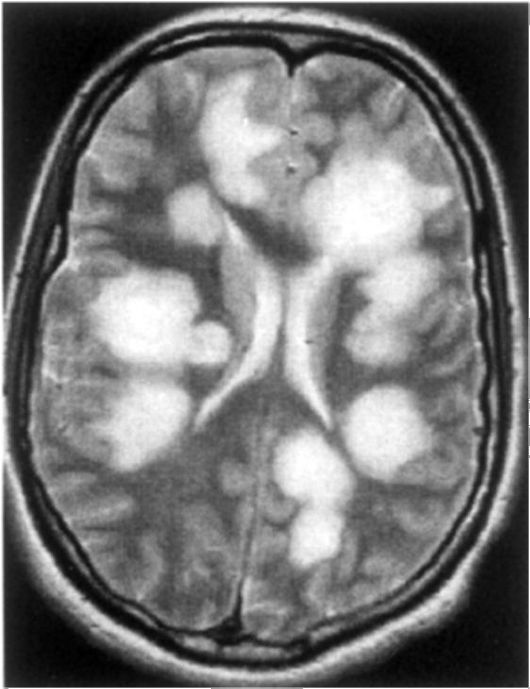

Информация о диссеминированном рассеянном энцефаломиелите